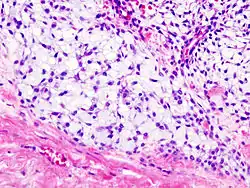

Histopathology